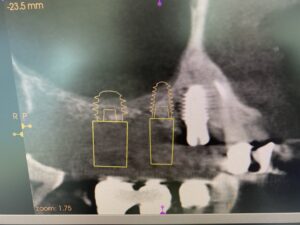

術前CT画像に示すよう、残存骨の高さは僅かしかないので、造骨の為にソケットリフトを併用しなければなりません。